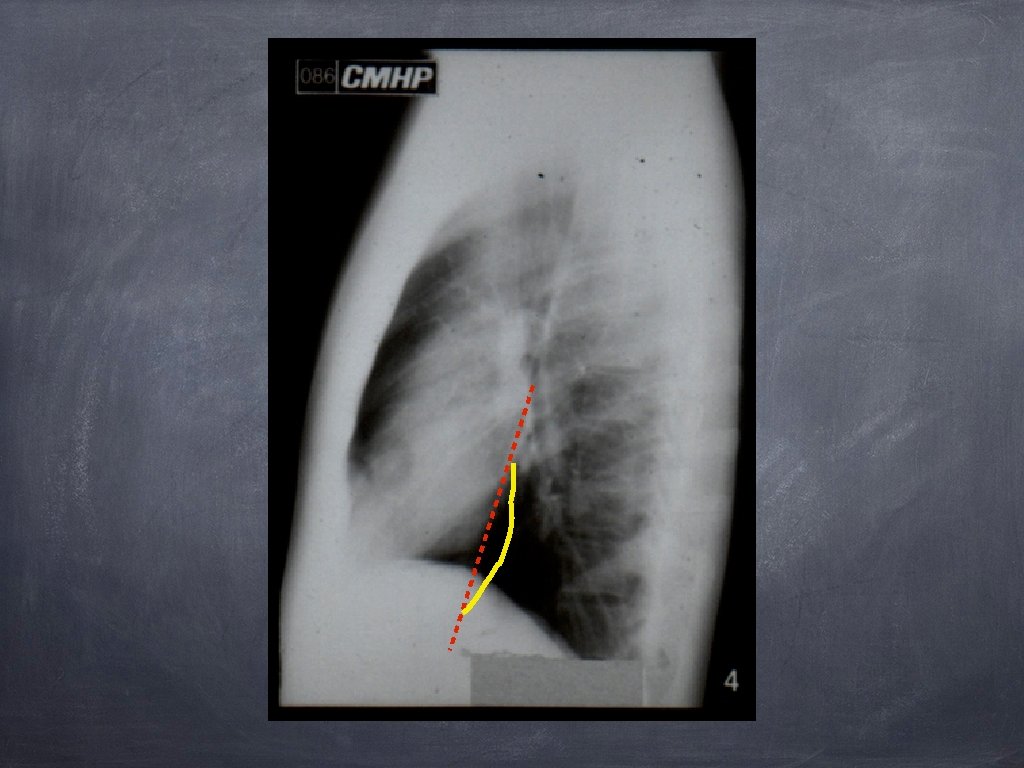

Hipertensiunea arterială pulmonară 1. Hiluri pulmonare cu arie de proiecție crescută, ramificate 2. Decalibrare bruscă a ramurilor de AP în regiunea perihilară; 3. Periferie pulmonară „săracă“ în benzi de desen pulmonar.